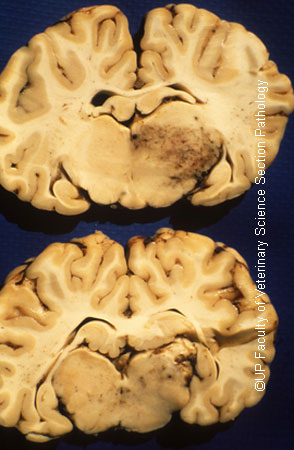

Turning sickness or cerebral theileriosis is an uncommon aberrant form of infection by Theileria parva or Theileria taurotragi in which lymphoblasts parasitized by schizonts accumulate in cerebral vessels leading to thrombosis and infarction. In the more acute form areas of intense congestion and haemorrhage are present in the meninges and brain which are associated with ares of softening (Infarction) and discoloration of brain tissue. Thrombosed meningeal vessels are often very promiment. There may be severe haemorrhage into the ventricles.

Turning sickness, Infarcts, Cerebrum